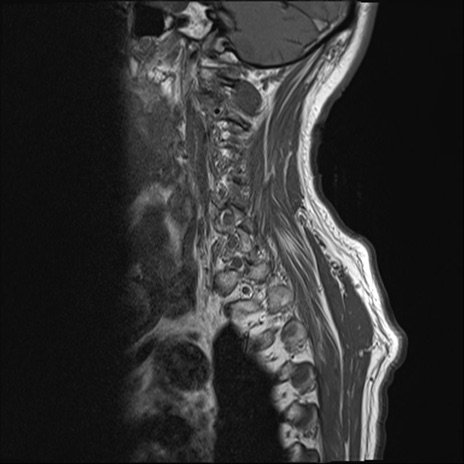

【整形】TIPS症例7 頚椎MRI T1WI(矢状断像)

頚椎MRI

T2WI(横断像)

T2WI(矢状断像)

矢状断像と横断像